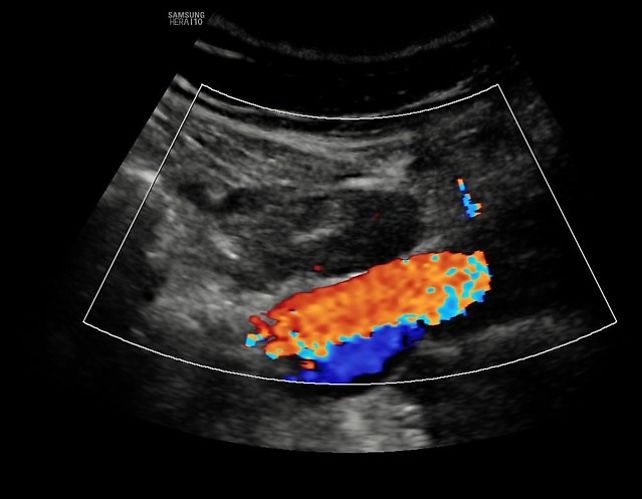

13

Pelvic (external iliac) lymph node with cortical thickening, visualized using a convex probe. Color flow represents iliac vessels.

14